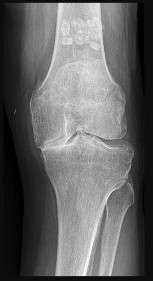

Figures 7a through 7d are the radiograph, MR images, and biopsy specimen of a 35-year-old man who has a painful, slowly enlarging knee mass. Which chromosomal translocation is characteristic of this pathology?

Synovial sarcoma is a soft-tissue sarcoma that usually occurs in young adults. Synovial sarcoma often causes pain, unlike most soft-tissue sarcomas, which generally do not cause pain. Imaging characteristics include soft-tissue calcifications on plain radiographs and a heterogeneous mass that is generally isointense to muscle on T1-weighted images and hyperintense to muscle on T2-weighted images. There are biphasic and monophasic types of synovial sarcoma. The biphasic

type, which is depicted here, has both spindle cell and epithelial components and will stain for both vimentin and cytokeratin. More than 90% of patients with synovial sarcoma have a characteristic genetic translocation of t(X;18), which results in the fusion protein SS18-SSX. This translocation can be stained for use of florescence in situ hybridization technology. t(11;12) is seen in Ewing sarcoma. T(9;22) is seen in extraskeletal myxoid chondrosarcoma. t(12;16) is seen in myxoid liposarcoma.